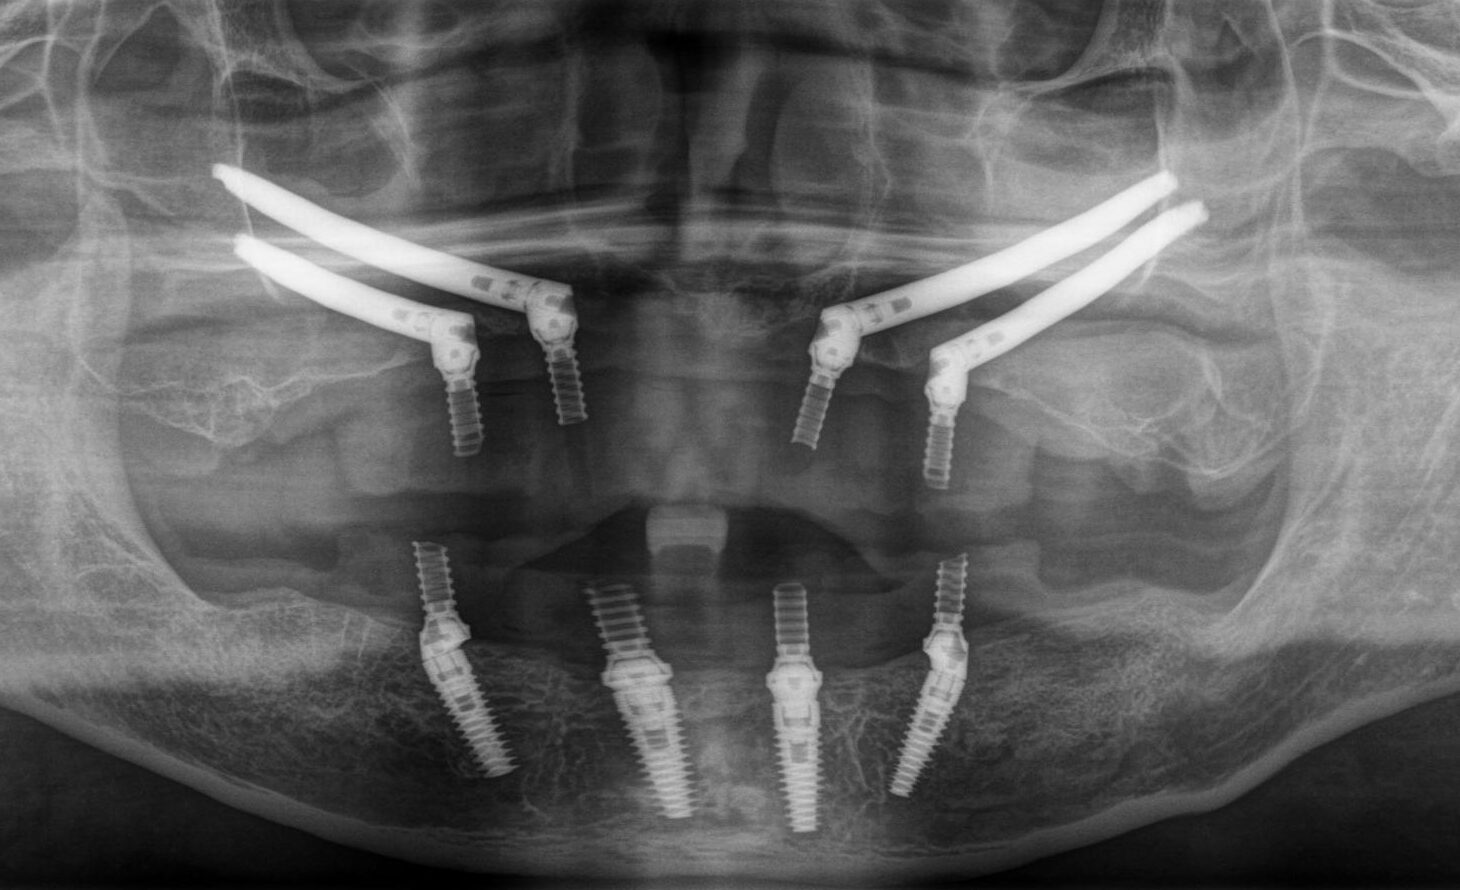

上下All-on-4

上顎:オールオン4ザイゴマ4本

下顎:オールオン4

Before

After

歯科医院にインプラントを相談しても「骨が全くない」「入れ歯しか無理」「オーバーデンチャー」と言われた患者さんのレントゲン画像です。